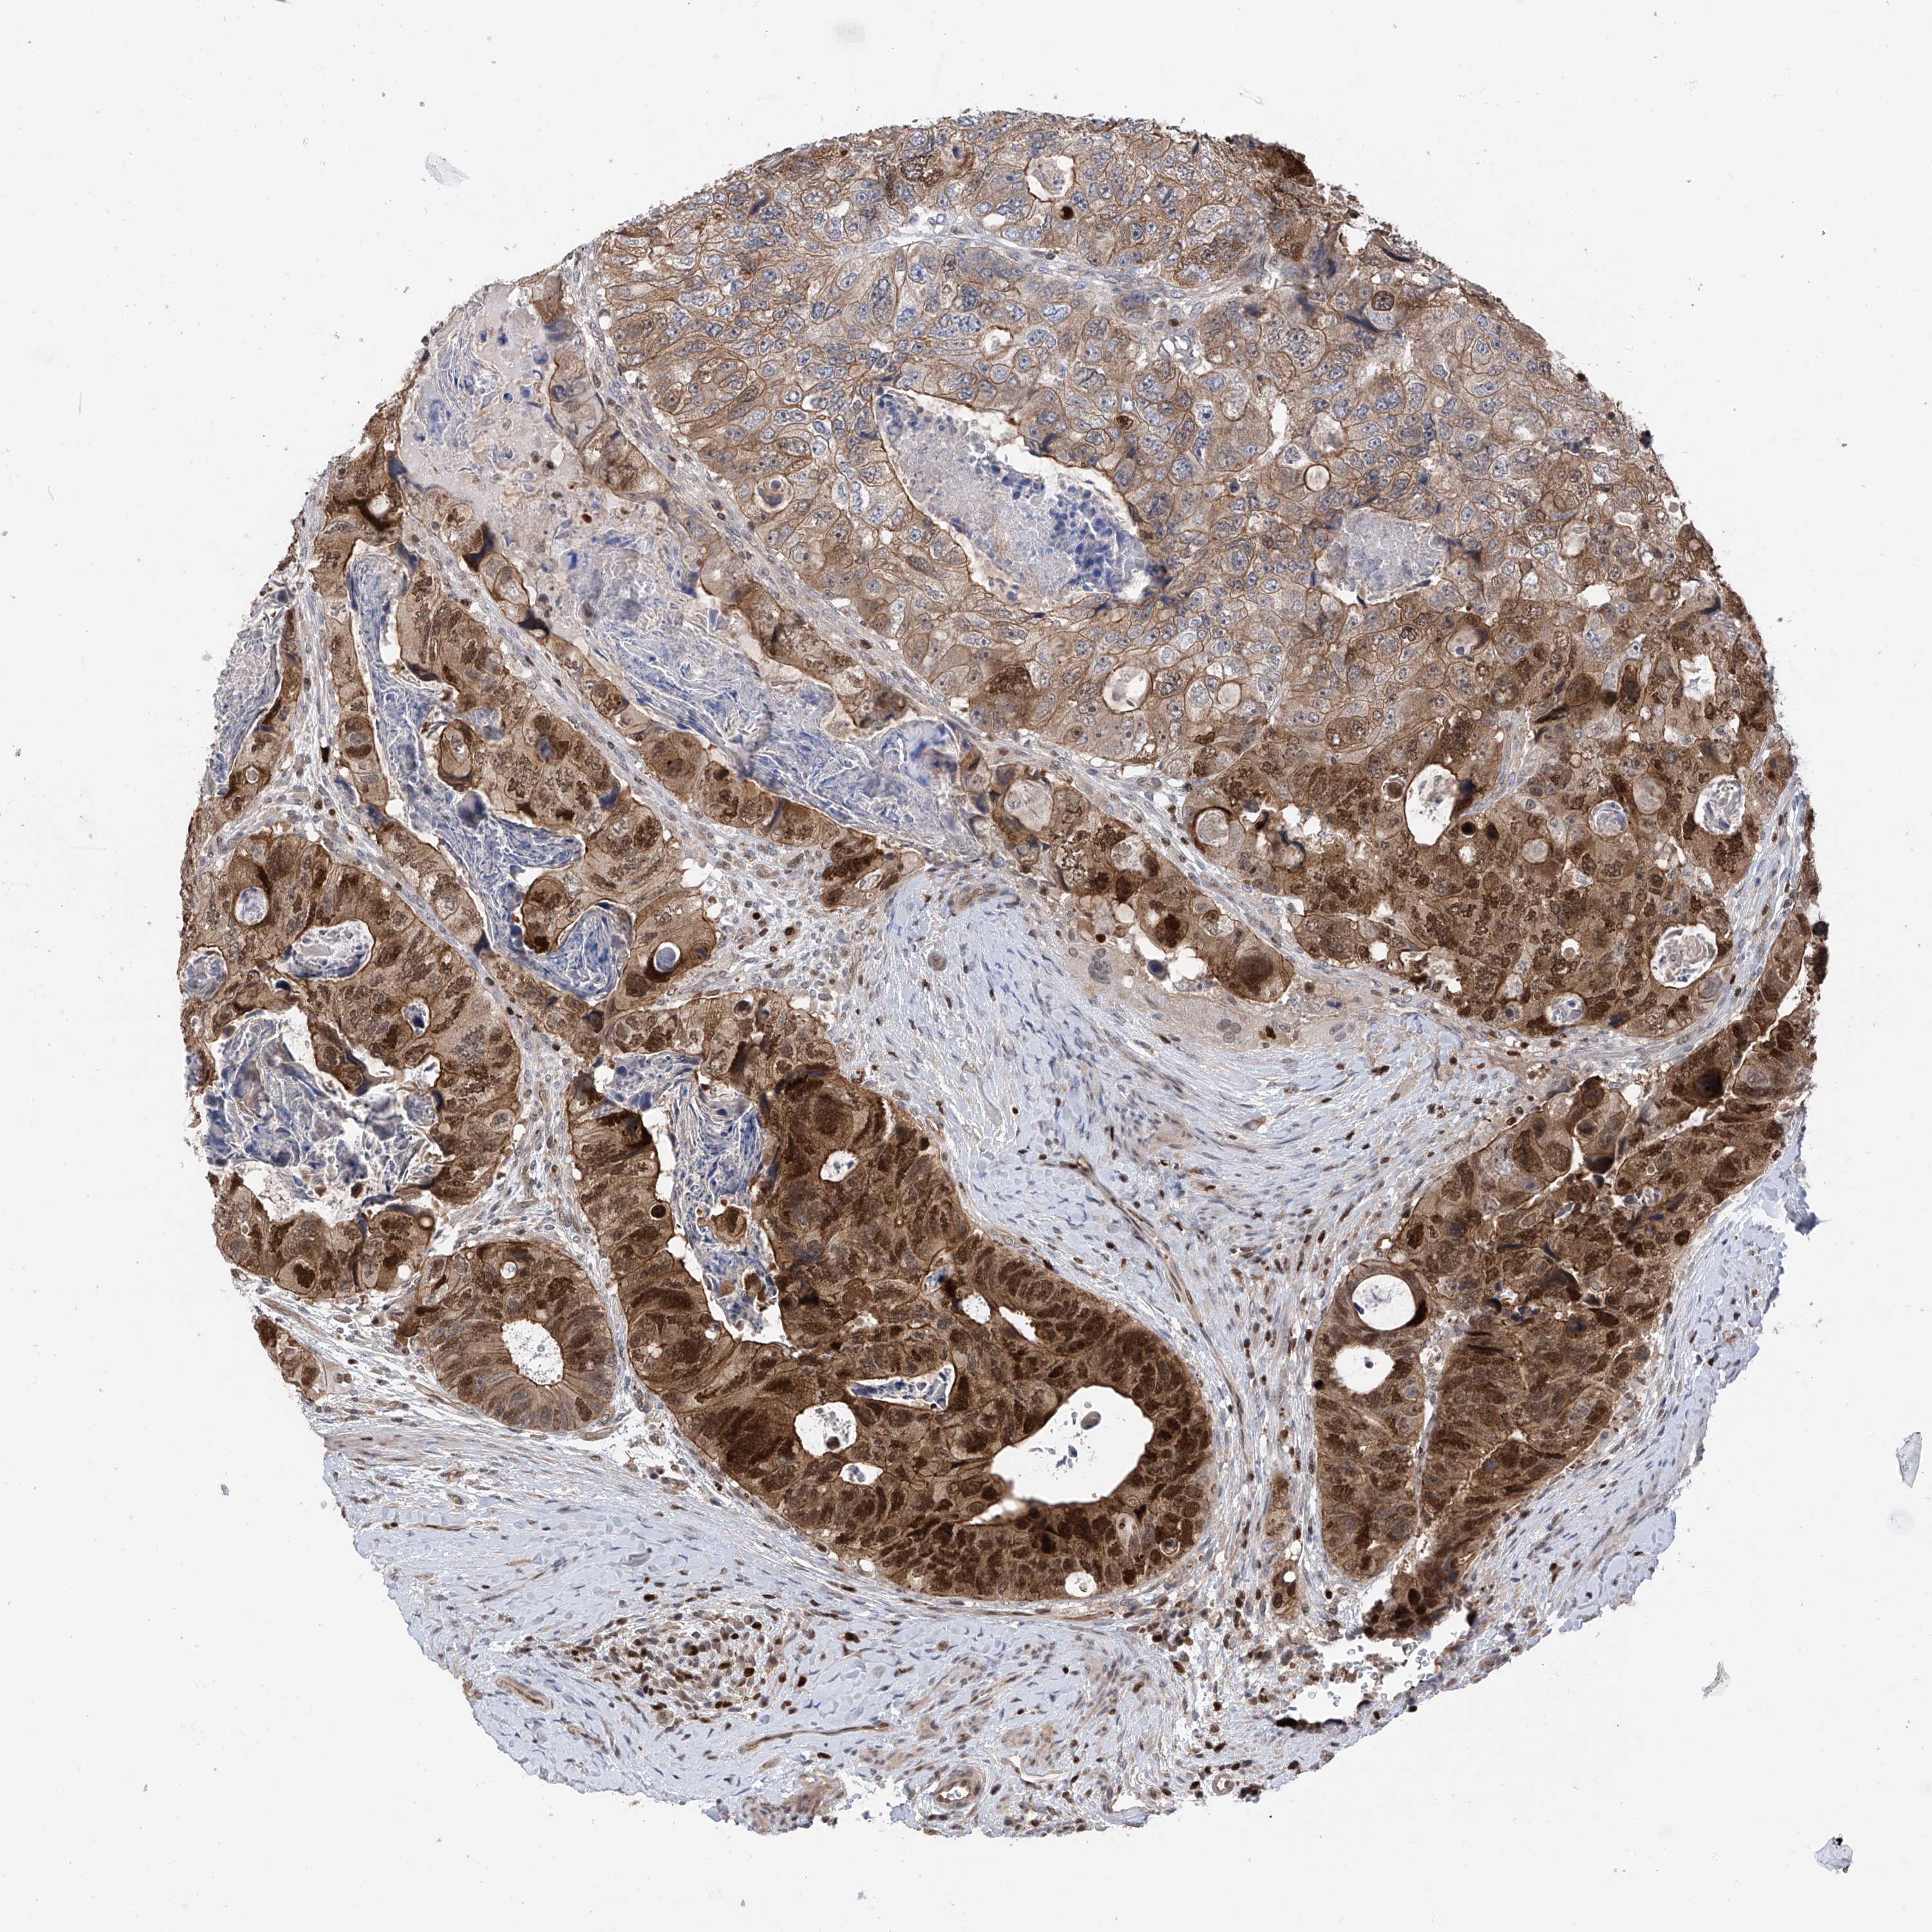

CANCER COLORECTAL CANCER Show tissue menu

Colorectal cancer

Rectum adenocarcinoma